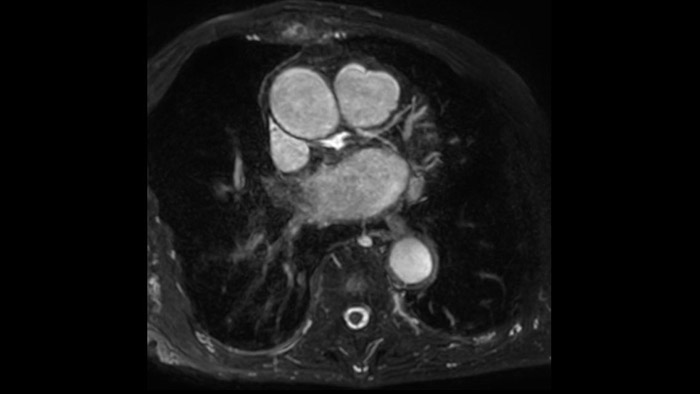

L'utilità diagnostica e prognostica della RM cardiaca è in continua crescita. È possibile valutare l'anatomia e la funzionalità cardiache utilizzando acquisizioni cine, ottenere informazioni sulla perfusione e vitalità del tessuto cardiaco, visualizzare potenziali edema con la sequenza Black Blood, accedere e persino quantificare la caratterizzazione dei tessuti con CardiacQuant.

IntelliSpace Portal MR CaaS5,6 Strain7 supporta nella diagnosi e nel monitoraggio dei pazienti fornendo parametri globali di strain, quali strain longitudinale globale (GLS), strain circonferenziale globale (GCS) e strain radiale globale (GRS), utilizzando immagini RM in asse corto e lungo e descrivendo inoltre la deformazione del miocardio, come il suo accorciamento, ispessimento e allungamento durante il ciclo cardiaco.